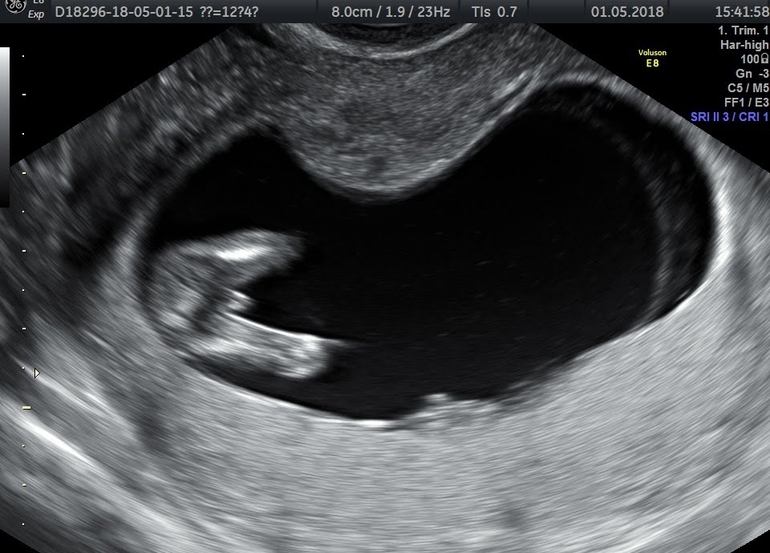

Сходила на первый скрининг!!

Результаты: УЗИ, КТГ, доплера, скринингаСлава богу по узи все отлично! Малыш активничал все время узи, так бы все и смотрела! Кровь пришла тоже без рисков - это главное))) пол мне предполагать врач не стала, сказала в это не верит)) но у меня руки то чешутся😀 посмотрите девченки, кто разбирается, тут почти 13 неделек)) видно ли чего?)))

Эм... Когда мне в первую Б делали скрининг на 13ой неделе, врач сказала, что скорее всего девочка, либо поздний мальчик, потому как у мальчика уже должно все формироваться начать к этому сроку, а у девочек начинает на недельку позже. На втором скрининге девочку подтвердили

Мне узист на первом скриниге,когда я спросила про пол,сказала, что смотреть там пока особо нечего. Типо невидно пока ничего